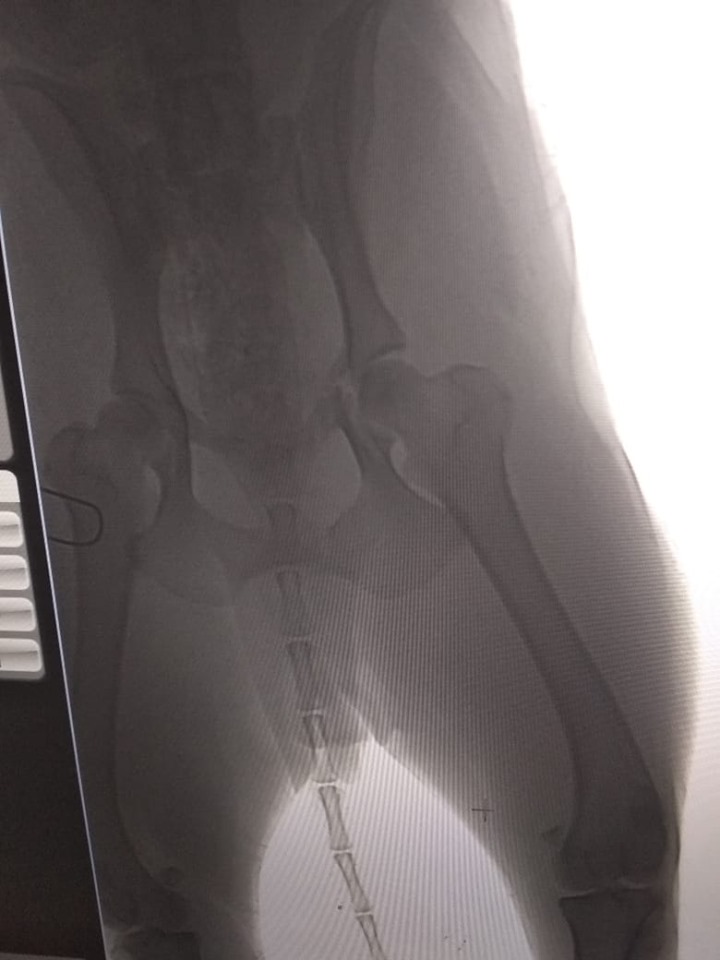

Трохи згодом тварина пішла на контакт тільки до одного з активістів чоловічої статті. Бідолашну відвезли до ветлікарні, де у неї діагностували перелом тазу.

Собачку назвали Дамбо, їй потрібен прихисток хоча б на декілька днів, допоки не зростуться кістки.